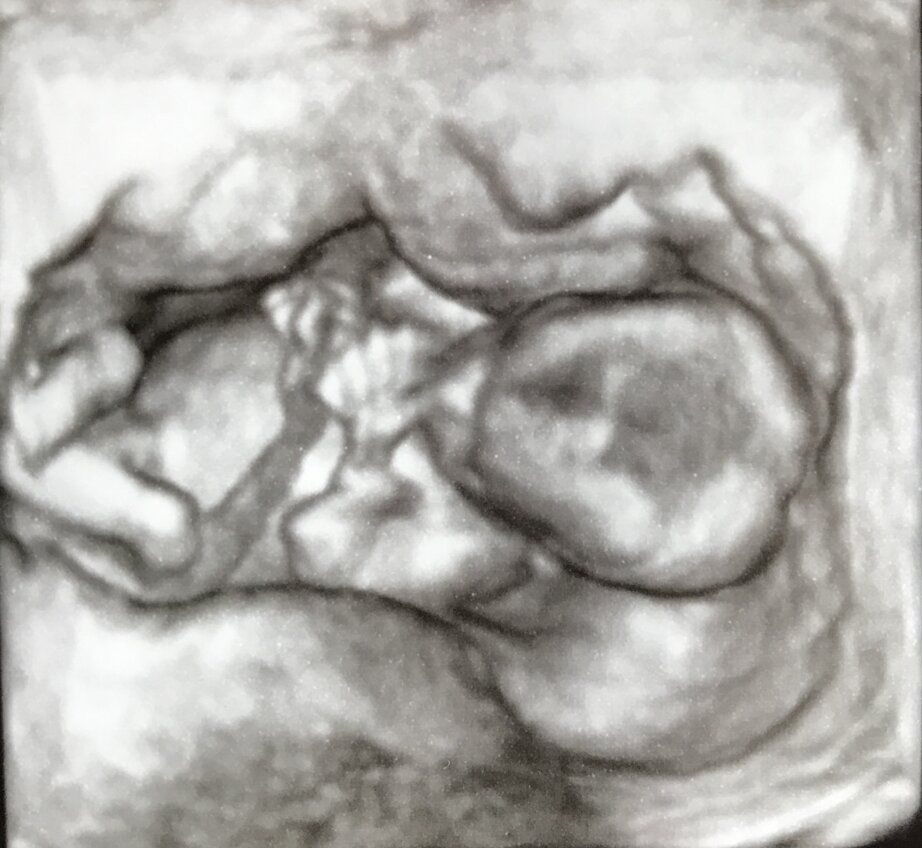

ECOGRAFIA 3D 4D